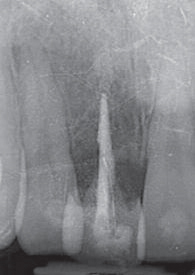

- 4a. De röntgenfoto van het moment van transplantatie en een foto 4 jaar later. Het element is verder geërupteerd, de wortelformatie is doorgegaan en de pulpaholte is geoblitereerd in het gedeelte dat afgevormd was bij transplantatie.

- 4b. De röntgenfoto van het moment van transplantatie en een foto 4 jaar later. Het element is verder geërupteerd, de wortelformatie is doorgegaan en de pulpaholte is geoblitereerd in het gedeelte dat afgevormd was bij transplantatie.